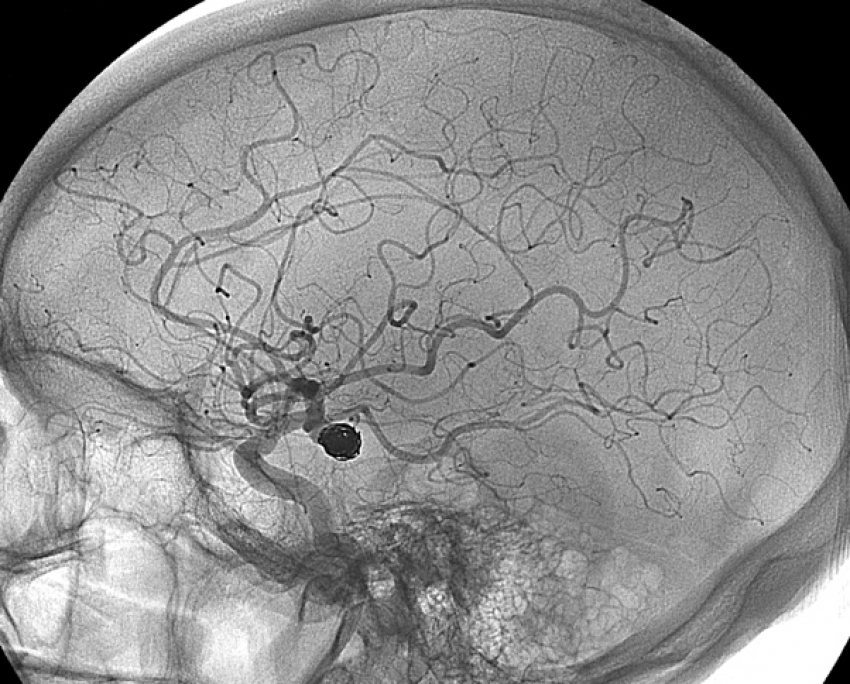

Diagnostic Angiograms

In this procedure, a catheter (a thin flexible tube) will be inserted into your leg or arm and the radiologist will flush a dye through the arteries to check blood flow and locate aneurysms, vascular malformations, blockages, narrowed vessels or other abnormalities.

Cerebral Aneurysm Coiling

This is a minimally invasive treatment for aneurysms that occur in the brain. A catheter is inserted through the skin into an artery and, using image-guidance, is maneuvered through the body to the aneurysm. Then, coils are inserted through the catheter and placed at the target site, to occlude the aneurysm. Blood clots around the coil(s), which helps block the flow of blood into the aneurysm and keep the vessel from rupturing or leaking.